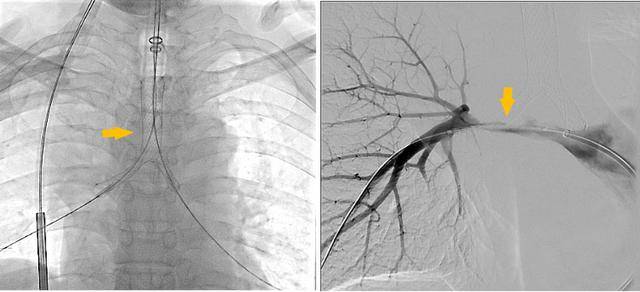

术前受压变窄的右肺动脉和中央气道

手术过程

同期置入支架后狭窄明显改善